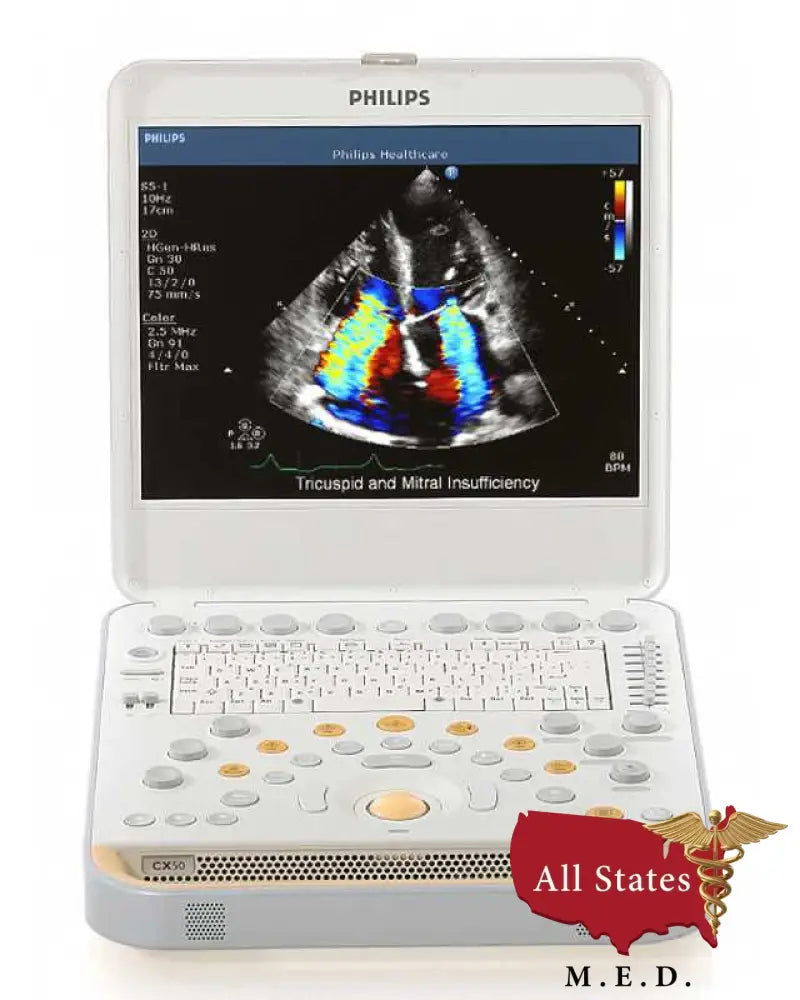

If you are looking for a powerful portable ultrasound with high-quality imaging and advanced features built-in, then the Philips CX50 is worth considering. Scroll below for more information about the CX50’s capabilities and specifications.

Philips CX50 Specifications

Next-generation all-digital compact broadband beamformer with pulse shaping capability.

Up to 504,576 digitally-processed channels.

Image presentation: Depth from 1 cm to 30 cm (transducer dependent.

Up to 170 dB full-time system dynamic range.

The CX50 system features a high resolution monitor for excellent viewing in the most difficult portable environments, and fast system start-up allows you to quickly begin your studies. Wireless and wired DICOM allow flexibility when connecting to your PACS. You can also export your data by DVD and USB media with integrated DICOM viewer.

Digital broadband beamforming on a compact